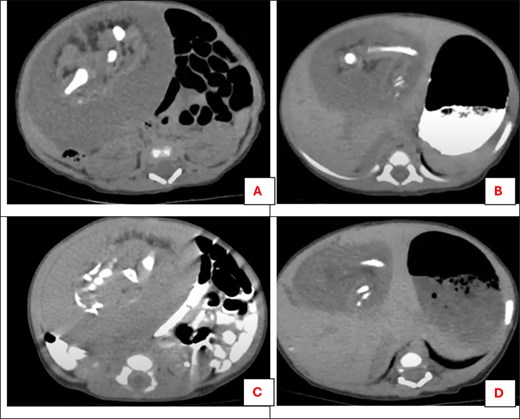

On evaluation, her routine blood investigations were within normal limits, and beta-human chorionic gonadotropin (β-HCG) was 8 mIU/ml, serum alpha-fetoprotein (AFP) was 39, 631 ng/ml and serum lactate dehydrogenase (LDH) was 434 U/L. USG Ultrasonography (USG) showed a large 8 × 6 cm, ill-defined heterogeneous mass in the right side of the abdominal cavity adjacent to the liver, having multiple hypoechoic areas and echogenic structures with internal vascularity. A contrast-enhanced computed tomography (CT) scan of the abdomen and pelvis revealed a large heterogeneous mass in the right side of the abdomen, measuring ~8 × 6 cm having cystic areas, fat attenuating areas, foci of calcifications, malformed skeletal parts resembling long bones, ribs, vertebrae, pelvic bones, and heterogeneous soft tissue fetal components. The mass resided in the right side of the abdomen, inferior to the liver displacing the loops posteriorly. It is fed by a large artery and draining vein along its posterior aspect. CT findings were suggestive of a FIF with various mass effects. Organized teratoma was kept as a differential diagnosis (Fig. 1). All lab and radiological investigations were fully funded by the government.

Post-contrast CT scan for the abdomen showing a heterogeneous soft tissue mass related to the lower part of the liver: (A) malformed skeletal parts resembling long bones, (B) cystic areas of fat attenuation and foci of calcifications of long bone, (C) malformed skeletal parts resembling three vertebrae, (D) cystic areas of fat attenuation.